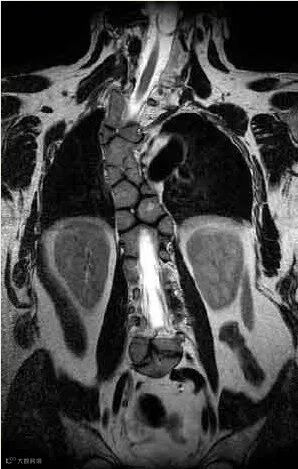

SCDO6型:复杂的颅颈交接区畸形,C1-C3的后半部分缺失,C4和T9为左半椎,T4为右半椎

SCDO6型患者多表现为颈椎椎骨缺失或融合等畸形,脖子短,运动受限。椎骨缺损会导致颈椎严重不稳定,在轻微的外部损伤后可能会导致心脏骤停。